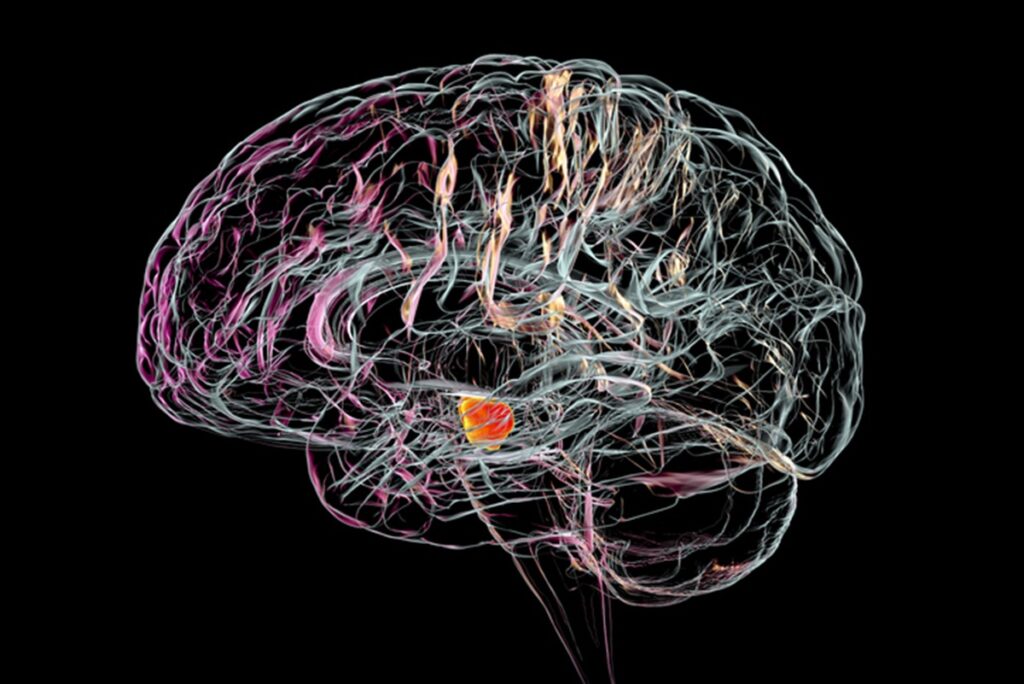

Parkinson é uma doença neurológica caracterizada pela degeneração progressiva dos neurônios responsáveis pela produção de dopamina

Esse processo degenerativo das células nervosas pode afetar diferentes partes do cérebro e, como consequência, gerar sintomas como tremores involuntários, perda da coordenação motora e rigidez muscular